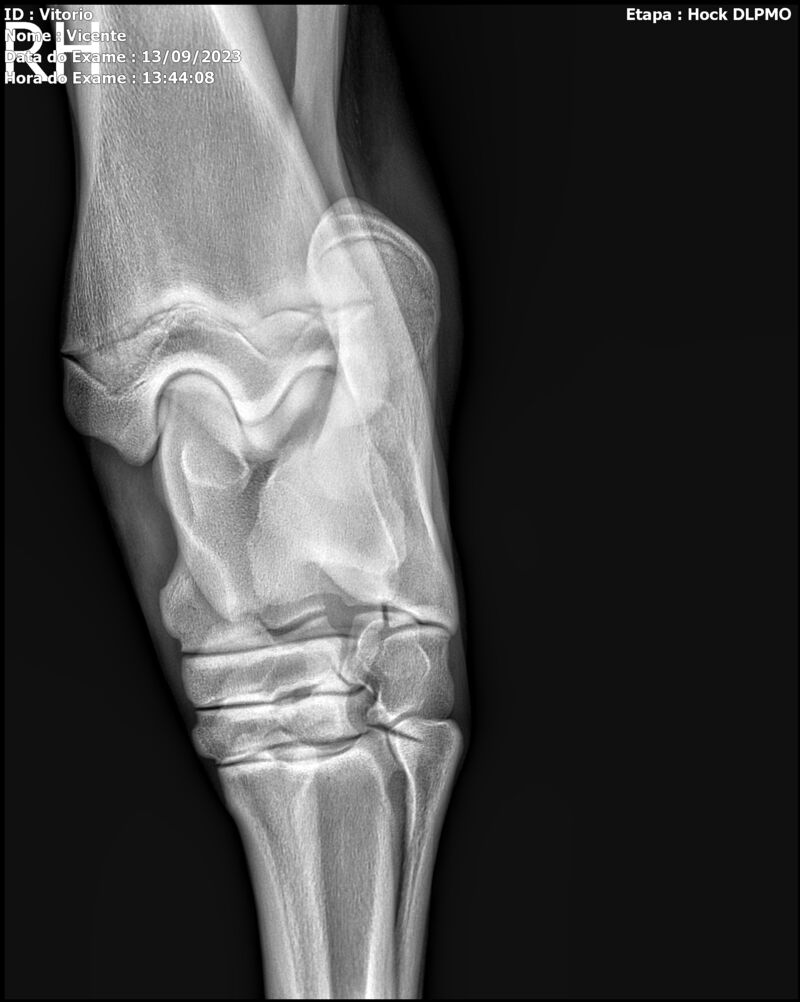

LOTE 13

THUNDER ZC

Raça: BRASILEIRO DE HIPISMO

Sexo: MACHO - POTRO

Nascimento: 17/09/2022

Altura Aproximada: 1,54

Pel.: CASTANHO

Registro: EM AND

Vend.: VICENTE CONTE

Local : PORTO FELIZ/SP